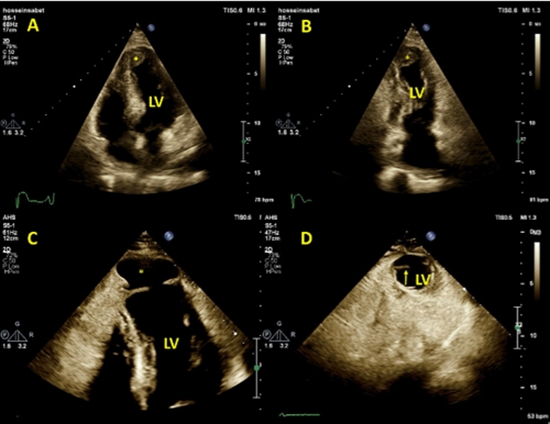

در یک مورد واقعی گزارش‌شده توسط پزشکان مرکز قلب تهران، مردی ۶۳ ساله با سابقه فشار خون بالا، پس از سکته قلبی گسترده، به بیمارستان مراجعه کرد. آزمایش‌های اولیه مانند نوار قلب نشان‌دهنده سکته بود و آنژیوگرافی عروق کرونر، انسداد عروق را تایید کرد. پزشکان با قرار دادن استنت، جریان خون را بازگرداندند. دو روز بعد، اکوکاردیوگرافی (سونوگرافی قلب) لخته بزرگی در نوک بطن چپ نشان داد و بیمار با داروهای رقیق‌کننده خون مانند آسپیرین و آپیکسابان مرخص شد.

اما ۱۹ روز بعد، تصویربرداری رزونانس مغناطیسی قلب (CMR) نشان داد که لخته برطرف شده، اما یک کیسه کاذب (پسودوآنوریسم) با اندازه کوچک در نوک قلب تشکیل شده است. این کیسه از پارگی دیواره قلب ایجاد می‌شود و توسط پریکارد (غشای اطراف قلب) و لخته محدود می‌ماند. اکوکاردیوگرافی دوم نیز این یافته را تایید کرد و وجود مایع در اطراف قلب (افیوژن پریکاردیال) را نشان داد که احتمالا از خونریزی ناشی از پارگی بود. بیمار بلافاصله جراحی شد و بهبود یافت.